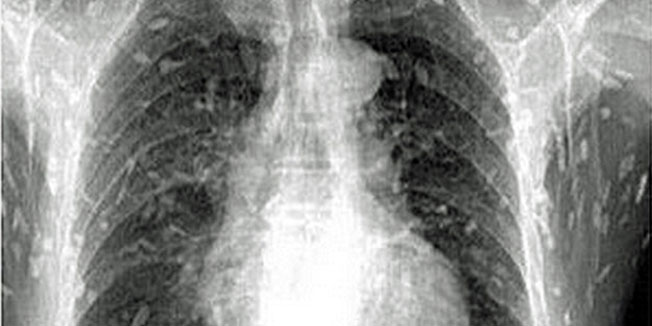

Kod Liaoa je parazit ušao u krvotok i raširio se tijelom, i tako uzrokovao cisticerkozu - infekciju koja, ako zahvati područje mozga, može biti smrtonosna.